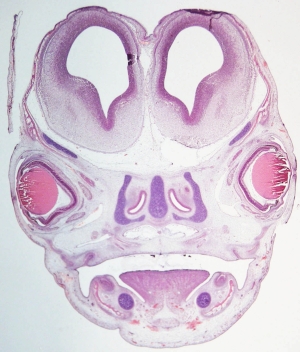

Stage 21

CfS 21

d37-39